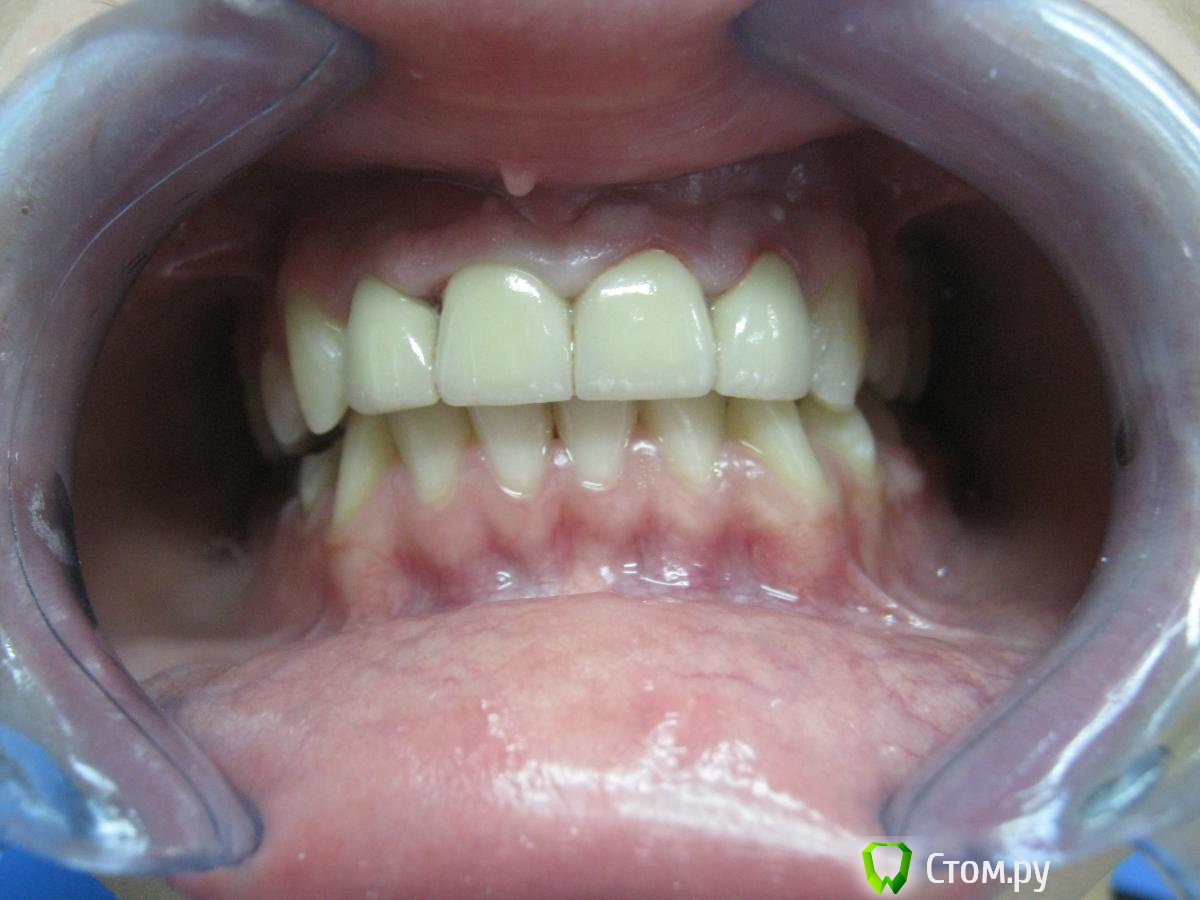

Abdul9848 Опубликовано 24 ноября, 2013 Поделиться Опубликовано 24 ноября, 2013 Выставляю на суд, фото препарированных культей скину позже.на зубах 11 21 культевые вкладки. 1 Ссылка на комментарий

ю.юрий Опубликовано 25 ноября, 2013 Поделиться Опубликовано 25 ноября, 2013 Выставляю на суд Нормально , для первого раза ,так даже хорошо , небольшой дисбаланс есть в пропорциях 1-х и 2-х зубов , но это к технику вопрос ... Ссылка на комментарий

Art 7 Опубликовано 25 ноября, 2013 Поделиться Опубликовано 25 ноября, 2013 Судя по форме зуба 1.2 до этапа протезирования можно говорить о том что форма имеющихся зубов не учитывалась при протезировании, так же можно было бы поработать с формой зуба 2.2 Ссылка на комментарий

ю.юрий Опубликовано 25 ноября, 2013 Поделиться Опубликовано 25 ноября, 2013 спрашивай) поясни.......Я так понимаю - техник ? Да в общем двойки слишком широкие широкие по отношению к первым . Пропорционально они должны укладываться в правила золотого сечения , более подробно загляни в личку , там есть книжка , на 202 странице есть рисунок и сама пропорция фронтальной группы . 1 Ссылка на комментарий

Джабраил Опубликовано 25 ноября, 2013 Поделиться Опубликовано 25 ноября, 2013 Я так понимаю - техник ? Да в общем двойки слишком широкие широкие по отношению к первым . Пропорционально они должны укладываться в правила золотого сечения , более подробно загляни в личку , там есть книжка , на 202 странице есть рисунок и сама пропорция фронтальной группы .да это техник.если так то форма 1.1 и 2.1 могла бы быть шире. вот почему я смоделировал 1.2 и 2.2 чуть шире.Как вы думаете на сколько рублей тянет эта работа(просто интересно) как вы думаете сколько стоит единица керамики для техника. И сколько врачу было бы не жалко дать за одну единицу в этой работе технику? Ссылка на комментарий